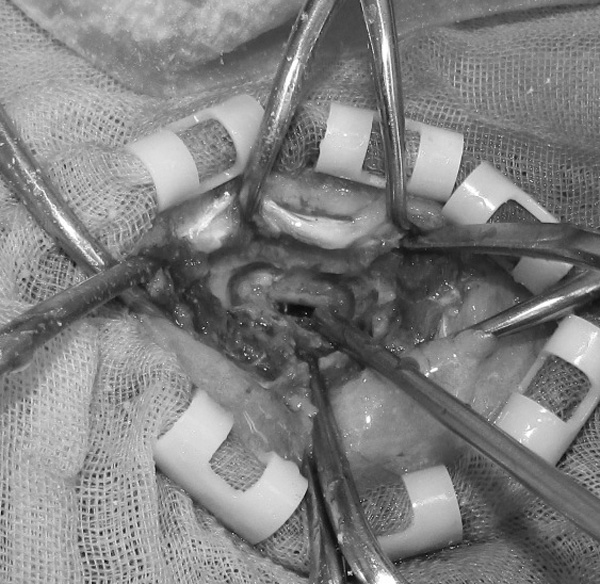

ワンちゃんが乳腺にできた複数のシコリを気にされて来院されました。bilateral mastectomyで対応しました。摘出後の病理組織検査の結果は、「R3-4間腫瘤:乳腺癌(複合型)」でそれ以外は「良性乳腺混合腫瘍」でした。無事元気に退院し、その後再発もなく経過は良好です。よかったね。